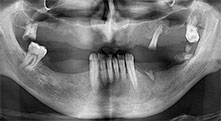

Bratu: Wir bevorzugen Knochenentnahmen von der Linea obliqua externa des posterioren Unterkiefers, nicht aus der interforaminalen Region. Nach der Weichgewebsinzision verwenden wir die neuen Sägen, um den Umfang der Knochenentnahme zu definieren. Wir erledigen damit in fast 80 Prozent der Fälle auch die gesamte Präparation. Zusätzlich verwenden wir eventuell andere Piezo-Instrumente und zuletzt einen Meißel, um den Block zu mobilisieren. Das ist für uns eine sehr effektive Operationstechnik.